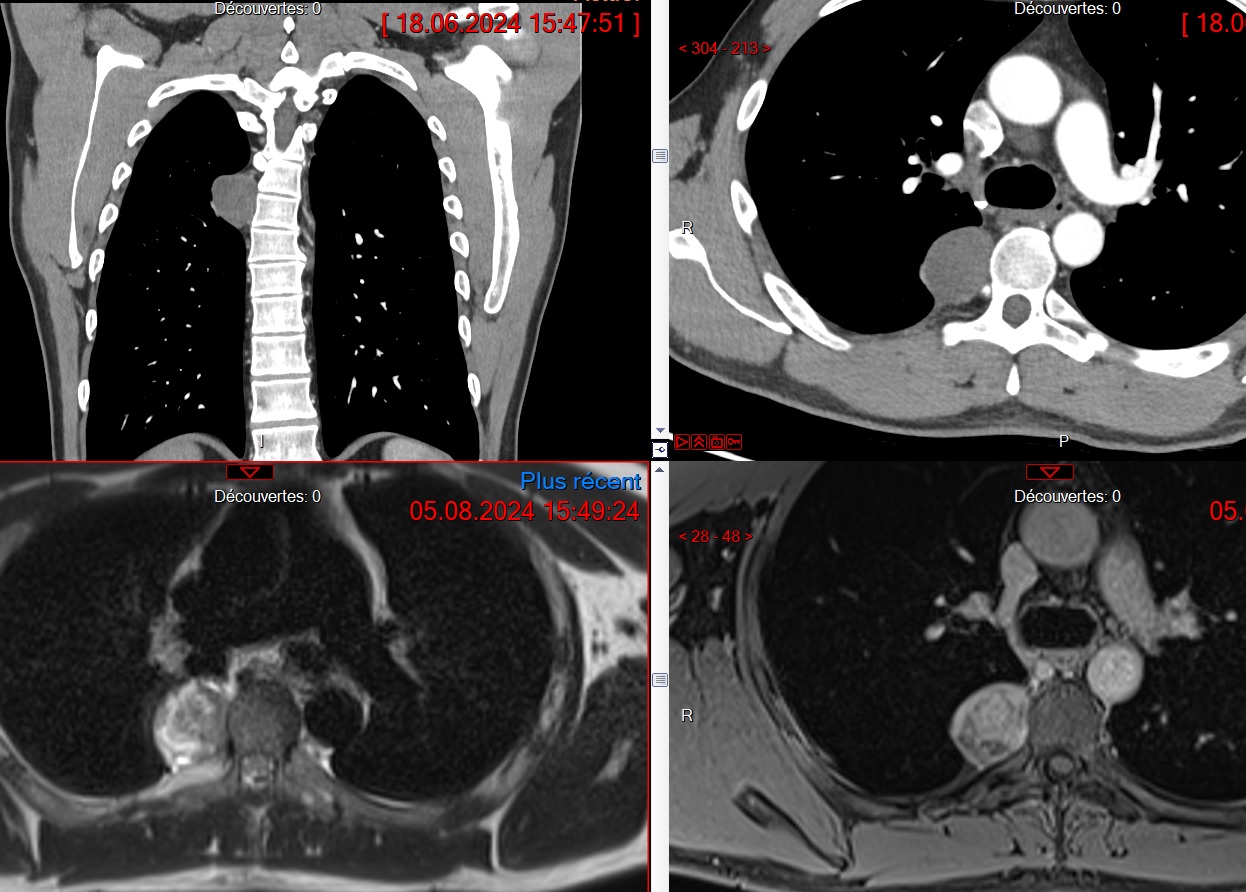

Cas

Masse Médiastinale Postérieure

Schwannome